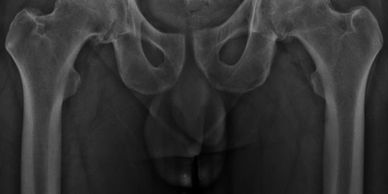

Artroplastía total de cadera izquierda

Paciente de 53 años, con artrosis bilateral de cadera . Se realizó un reemplazo total de cadera izquierda no cementada.